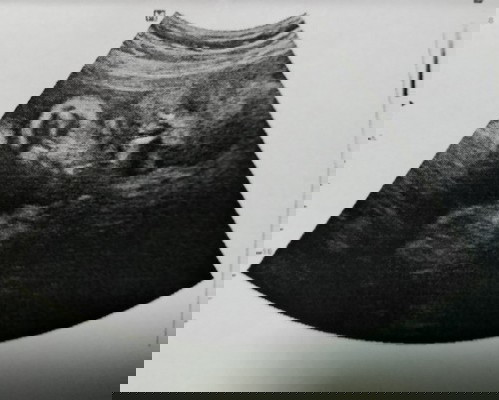

31สัปดาห์5วัน

น้อนนอนสบายใจ แต่แม่กลุ้มต้องเจาะเบาหวานอีกรอบ